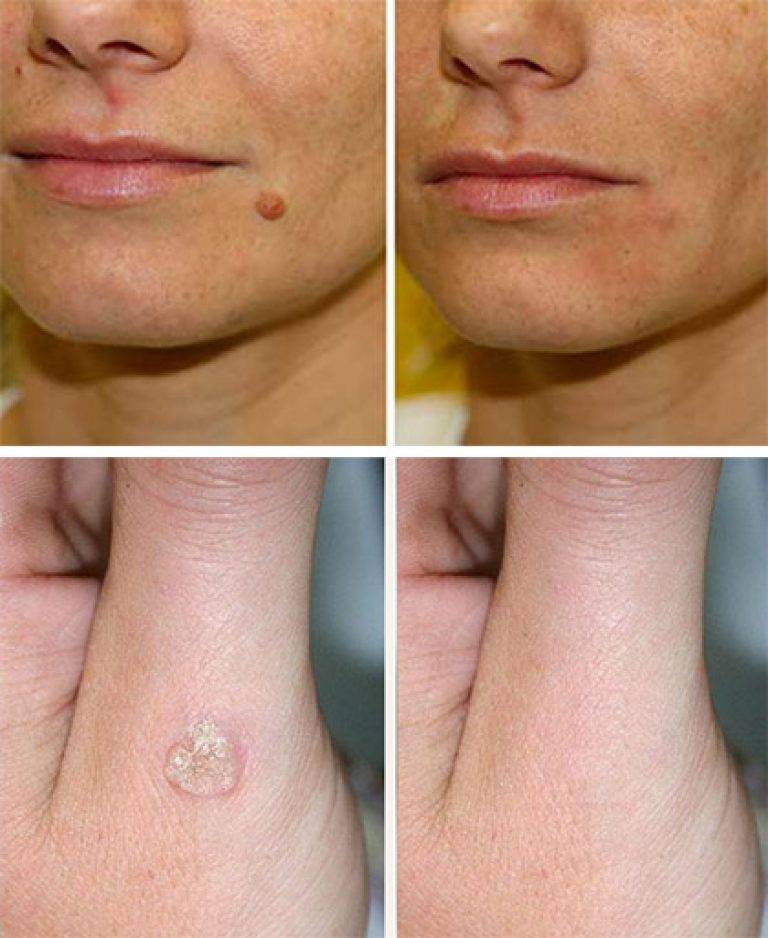

Фото: метод криодеструкции

Фото: лазерное удаление

Фото: после лазеротерапии

Фото: рубец на коже после удаления новообразования

Фото: после удаления на теле образуются корочки, которые нельзя удалять